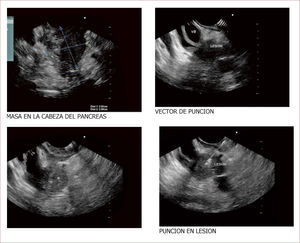

Otra cosa importante en estos casos es que el EUS, permite ver compromiso de órganos vecinos, compromiso de ganglios y así mismo ver la vía biliar, el Wirsung y los vasos, siendo el más importante la porta. Estos datos hacen que podamos hablar de resecabilidad o no y del tipo de cirugía que se tenga que realizar 40,41. Figuras (10-12).

Masa de cabeza de PÁncreas en un hombre de 47 años

Compromete vía biliar y tiene múltiples adenopatías. Se ve también involucrado el Wirsung. La patología reportó un adenocarcinoma mal difereciado del páncreas. En la foto A se ve la masa y en está igual que en la de la derecha se ve que contacta e invade la porta. En la B se ve un nódulo grande entre la porta y la lesión de la cabeza. Con estos hallazgos más la clínica del paciente el grupo de cirugía decidió manejo paliativo. Colocamos en vía biliar un stent autoexpandible no recubierto. El paciente está aún en seguimiento. (imagen de Unión de Cirujanos SAS – Lázaro Arango (Autor), se publica con permiso).